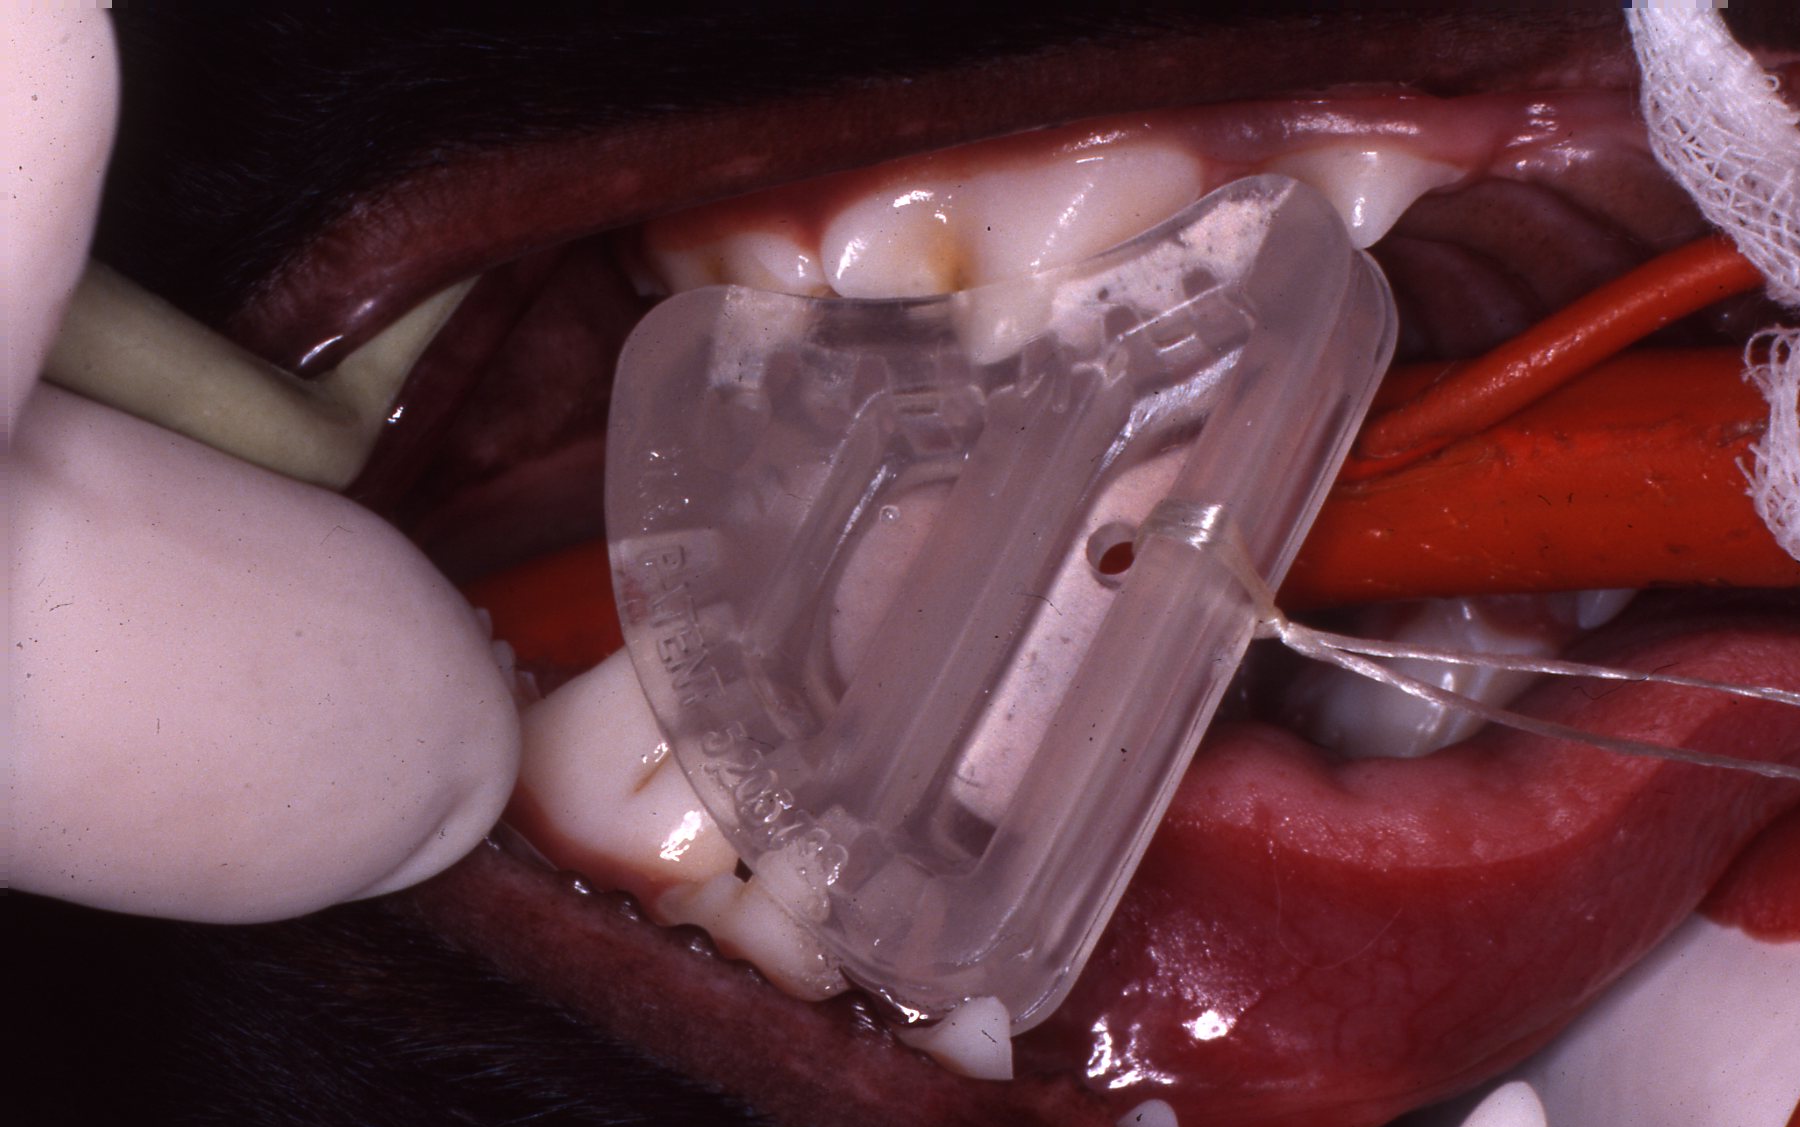

Herbivores, in particular ruminants for example, must be able to masticate their food in order to digest it to survive. Most primates and carnivores can be fed food in compositions that do not have to be chewed and they will be able to digest and survive. Therefore, extraction of herbivores posterior teeth is only done when absolutely necessary. Particular teeth, such as mandibular canines and carnaissals in carnivores are especially important to their jaws physical integrity. Therefore, endodontics will be seriously considered to maintain them. Of course there are always exceptions to consider. I review animal groups and particular species relative to these treatment considerations in another section.

I usually only consider relatively simple procedures or restorations on animals. If I can simply polish smooth a sharp or rough enamel fracture, I will do that rather than place a restoration. Functional durability is my only consideration of restorations in animals.

I have placed full cast crowns on dogs trained in law enforcement. I have provided crowns that remained in place for the remainder of the dogs' career, permitting challenging duty functions. Other than on law enforcement dogs, my philosophy toward performing the multiple anesthesias (or a very long single anesthesia) required to provide a crown would only be warranted in a very few situations. These would be considered on a domestic or captive exotic animal canine or perhaps a carnaissal tooth that has had an endodontic prodecure on a relatively young animal. I have observed endodontically treated teeth in such animals fracture after several years. They became infected and had to be removed. A conservatively shaped full cast crown would serve well to avoid this complication.